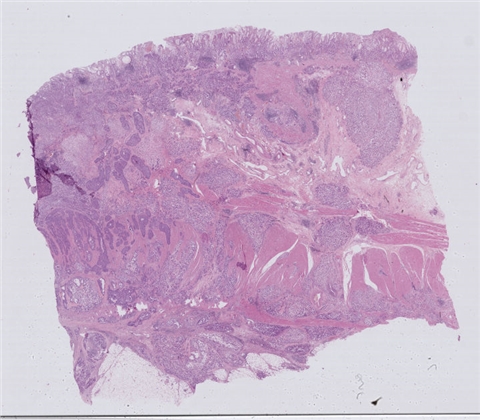

患者详情: 发现肛门肿物8月余,大便带血次数增多。外院病理检查:腺癌伴类癌分化。

大体所见: 肠管一段,直径3cm,长22cm,紧邻肛侧切缘、距另一侧切缘19cm处可见一菜花样肿物,大小6*6*5cm,切面灰白灰红色,质脆,侵及肠管全层,共取11块。

免疫组化: 蜡块一:CD20(-)、PAX-5(-)、CD3(-)、CD43(-)、EMA(局灶弱+)、CKL(-)、CK8/18(+)、CgA(-)、syn(+)、CD56(+) 蜡块二:GST-π(+/-)、TOPOII(+)、PGp(3+)、EGFR(-)、VEGF(+/-)、P53(小于3%+)、CERbB-2(-)

医院: 九江学院附属医院